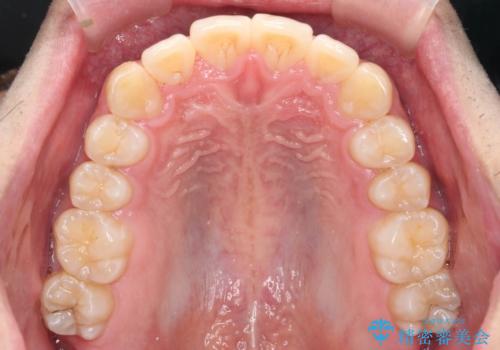

マウスピース矯正で前歯の角度、ガタガタをきれいに

- 突き出た前歯の角度、歯ブラシのしづらい前歯のがたつきの改善を希望され来院されました。

4本の小臼歯を抜きワイヤー矯正治療、下顎前歯を1本抜去しマウスピース治療のメリットデメリットを検討・相談し、より歯を抜く本数の少ないマウスピース矯正を行うこととなりました。

下顎の前歯は1本だけ抜去せざるをえませんでしたが、4本の小臼歯抜去とマルチブラケット矯正を回避することができ、治療結果・過程に満足いただくことができました。